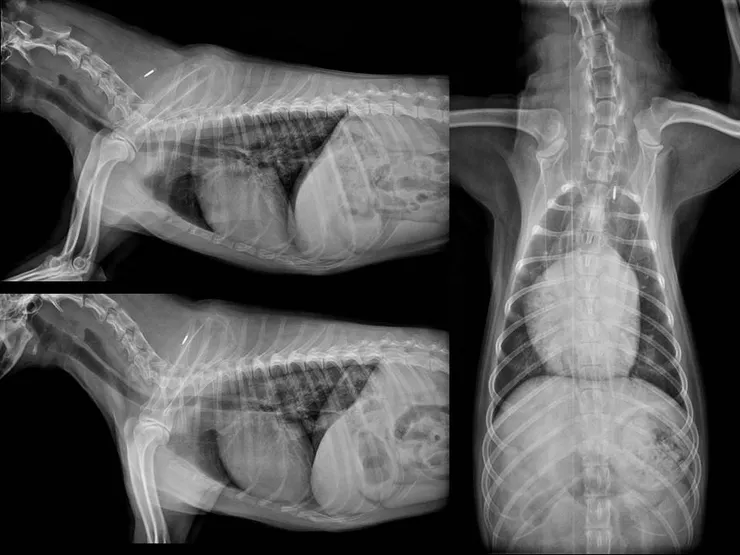

就診時可以注意到小朋友在診間的呼吸速率都蠻急促的,拍攝完三個方向的X光後則可以看到整段食道內充滿了空氣伴隨著部分肺部實質的變化。到了這邊大概也不用在做什麼無謂的造影檢查來增加動物嗆咳吸入造影劑的風險,可以放心地說出:啊呀,是個巨食道呢!